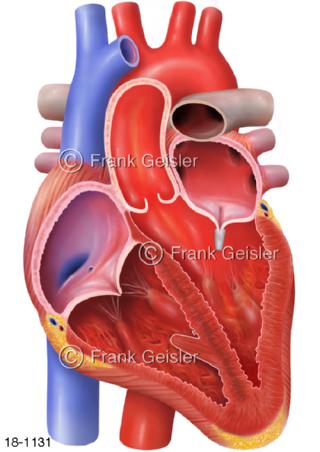

18-1131 Herz Insuffizienz Herzklappe mit MitraClip